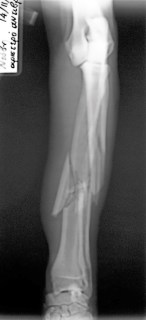

Συντριπτικό κάταγμα αντιβραχίου σε σκύλο από Πέτρος Μπεάκος08/01/201407/12/2017Σχολιάστε Προσθοπίσθια ακτινογραφία Πλάγια ακτινογραφία Οστεοσύνθεση κερκίδαςμε πλάκα και βίδες καιωλένης με ήλο και σύρμα Κοινοποιήστε: Στείλε ένα σύνδεσμο σε έναν φίλο(Ανοίγει σε νέο παράθυρο) Email Εκτύπωση(Ανοίγει σε νέο παράθυρο) Εκτύπωση Mοιραστείτε στο Facebook(Ανοίγει σε νέο παράθυρο) Facebook Μοιραστείτε στο X(Ανοίγει σε νέο παράθυρο) Χ Μου αρέσει! Φόρτωση... Σχετικά